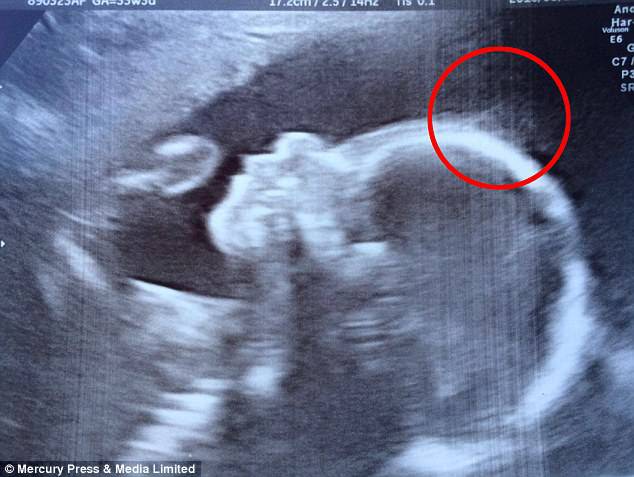

Quando fate l’ecografia dei vostri figli di solito non si capisce poi molto: io per entrambe le gravidanze cercavo di capire che cosa stesse guardando il ginecologo ma mi sembrava davvero impossibile. Figuriamoci allora la sorpresa che hanno avuto Natasha e Ashley quando hanno visto qualcosa di decisamente singolare nell’eco della loro bambina.

Natasha Gent, di 28 anni  da Medway, nel Kent, si è sentita dire dai medici di  aspettarsi un bambino con ‘un po’ di capelli’ dopo che hanno rilevato delle ciocche intorno alla testa della figlia Holly durante l’ecografia a 20 settimane.